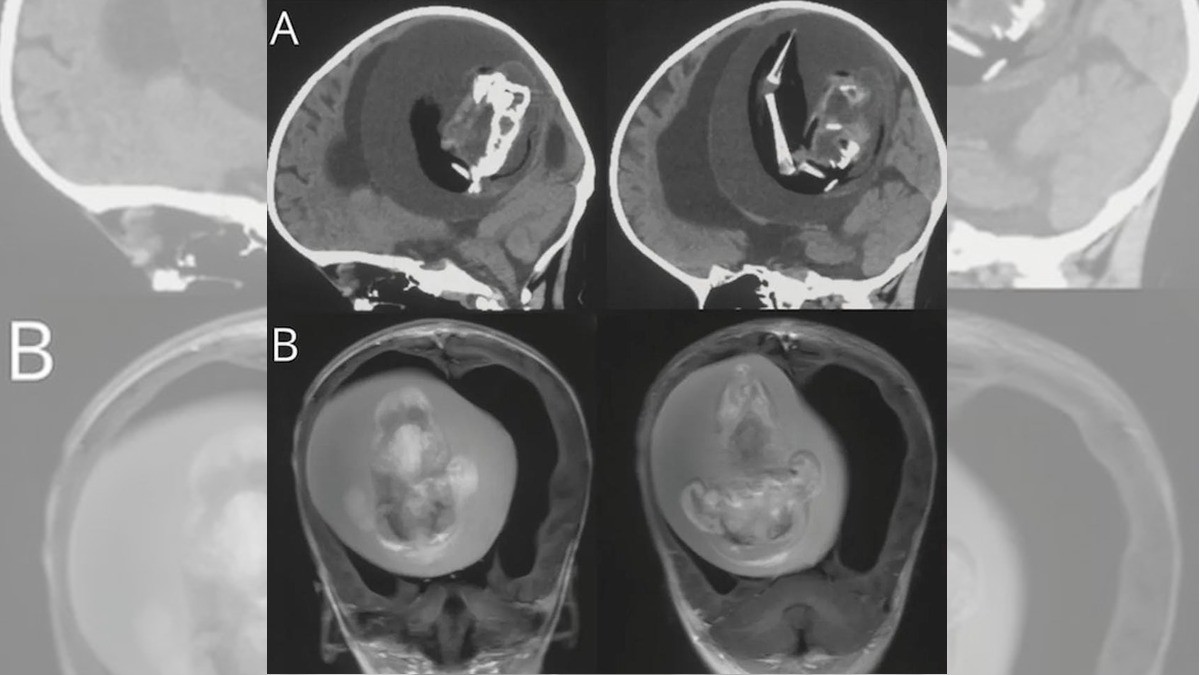

Los médicos se percataron de la situación cuando la niña comenzó a presentar síntomas de retraso en el desarrollo de sus habilidades motoras, así como por un agrandamiento extraño craneal y acumulación de líquido en el cerebro.

Una vez realizados los estudios, decidieron hacer la cirugía donde localizaron al gemelo, mismo que ya mostraba dos huesos de la pierna, una columna vertebral y dedos en las extremidades superiores.

Tas la operación, le realizaron pruebas de ADN al feto, con lo que se confirmó que se trataba del gemelo de la niña, el desarrolló debido a la sangre de su hermana.